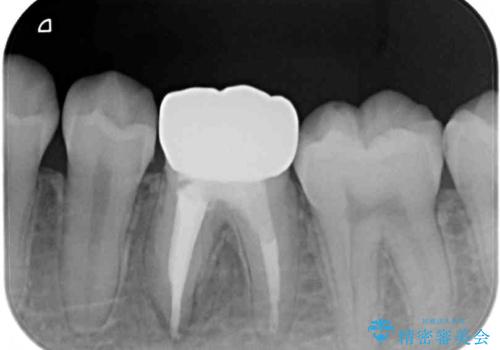

患者様と相談し、根管治療を再度行った後、フルジルコニアクラウンにて補綴治療することとしました。

フルジルコニアクラウンを装着したことにより、舌感が改善されるとともに、むし歯再発リスクを軽減することができました。